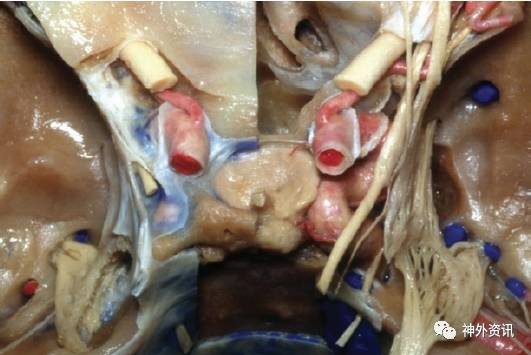

图6. 前床突切除术后获得的暴露。注意颈内动脉床突段的广泛暴露(左图)。视神经与前床突紧紧相邻,这使得术中磨除前床突时易损伤视神经。床突间隙的上界和外侧界为额颞部硬脑膜。眶筋膜、视柱和蝶骨构成前界和下界。

去除其他骨性及膜性结构后可显露其他相关的重要结构(注意走行于海绵窦外侧壁内的颅神经)(右图)。去除前床突时有损伤这些结构的风险。(感谢AL Rhoton, Jr教授对图片的授权)